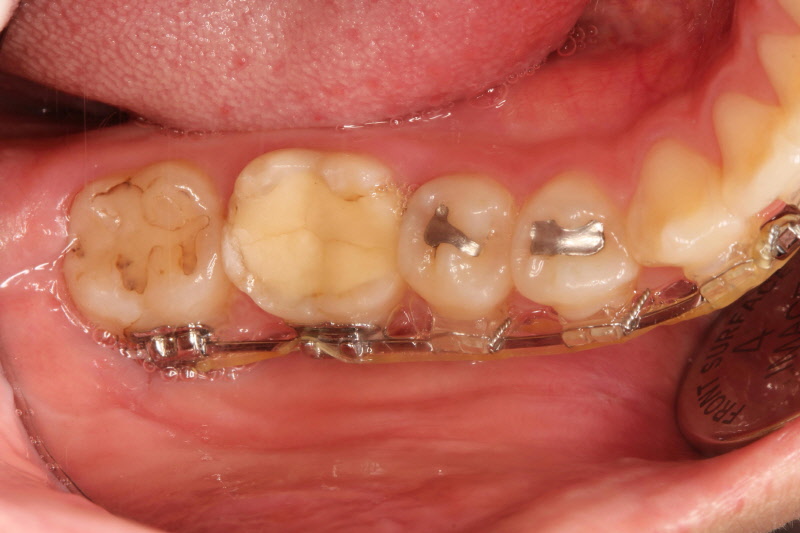

시간이 지난 후에도 좋은 상태를 유지하고 있는 아말감